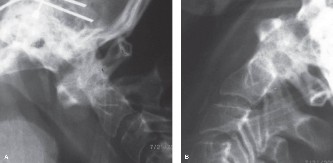

The diagnostic imaging workup for this patient spanned his initial presentation at age 15 and his subsequent return at age 20, providing a textbook illustration of the natural history of untreated isthmic spondylolysis. During his initial visit, standard weight-bearing anteroposterior (AP), lateral, and bilateral oblique radiographs of the lumbar spine were obtained. The lateral radiograph demonstrated a normal lumbar lordosis and preserved L5-S1 disc space height, with no evidence of anterior translation (spondylolisthesis). However, the oblique radiographs revealed the pathognomonic "collar on the Scotty dog" sign. The "Scotty dog" represents the posterior elements of the vertebra, where the nose is the transverse process, the eye is the pedicle, the front leg is the inferior articular process, and the neck is the pars interarticularis. A radiolucent line across the neck confirmed the presence of bilateral L5 pars defects.

Upon his return five years later, the imaging profile was drastically different. Standing lateral radiographs now revealed a Meyerding Grade 2 spondylolisthesis at L5-S1, indicating that the L5 vertebral body had translated anteriorly by 25% to 50% over the sacral promontory. Furthermore, there was a noticeable collapse of the L5-S1 intervertebral disc space, signifying advanced degenerative changes secondary to the altered biomechanics and chronic instability. We also meticulously measured the patient's spinopelvic parameters on a standing 36-inch scoliosis cassette. His Pelvic Incidence (PI) was measured at 65 degrees (high), which mathematically dictates a higher Sacral Slope (SS) and Pelvic Tilt (PT). A high PI is a known biomechanical risk factor for the progression of spondylolisthesis, as it creates a steeper lumbosacral shear angle, placing immense anterior translational force across the compromised L5-S1 segment.